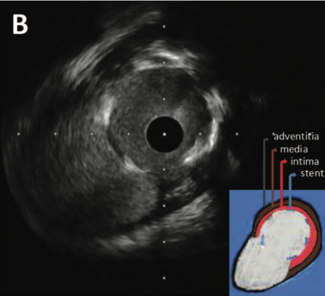

The utilization of coronary atherectomy continues to increase in modern percutaneous coronary intervention. To further improve safety and simplify delivery of the Cardiovascular Systems, Inc. (CSI) orbital atherectomy system, we present a...